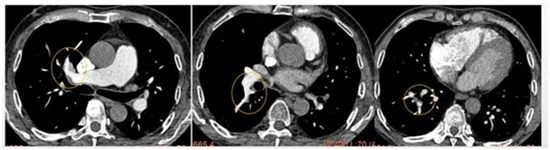

▲ 术前肺动脉CTA,肺动脉主干多发血栓

▲ 经抗凝溶栓治疗后,肺动脉血栓基本消失